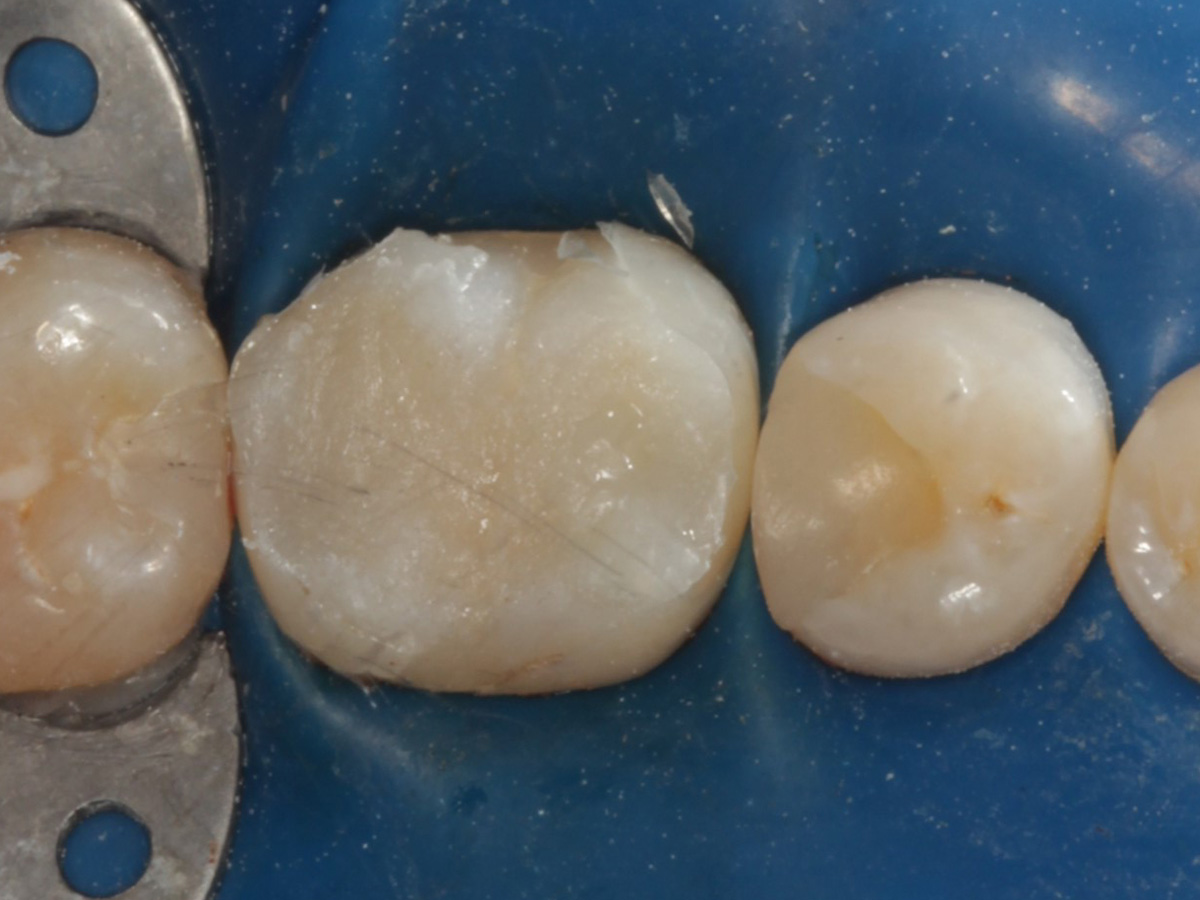

Kavitäten gefüllt (Injektion Moulding: Flowkomposit, erwärmtes Seitenzahnkomposit aus Karpule)

Abbildung 20

Abbildung 21

Zahnseidenkontrolle: kein Überschuss, satte Kontaktpunkte

Abbildung 22

Fertige Restauration Zahn 46